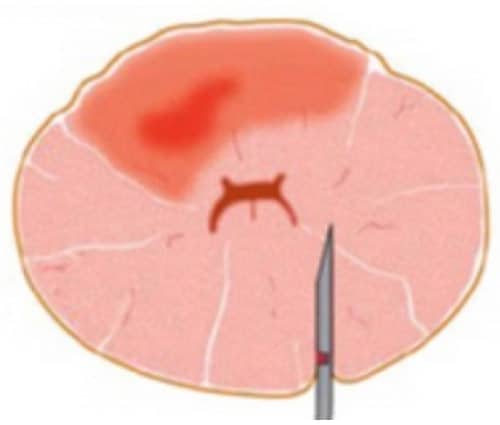

Am bekanntesten ist die sogenannte MRT/US-Fusionsbiopsie, bei der die MRT-Bilder der Prostata mit den real-time Ultraschallbildern, die während der Biopsie aufgenommen werden, überlagert – fusioniert werden. Und da liegt das Problem. Während die MRT-Bilder starr die Anatomie der Prostata während der MRT-Untersuchung wiedergeben, ändert die Prostata bei einer Biopsie ständig ihre Form. Denn die Prostata hat weiche und harte Anteile und ist gleichzeitig elastisch wie auch plastisch verformbar. Daher passen die MRT-Bilder und US-Bilder nicht zusammen.

Mit Hilfe sogenannter elastischer Fusionsalgorithmen hat man versucht, dieses Problem zu lösen. Ohne Erfolg. Daher wird die tatsächliche Fusionsbiopsie immer mehr durch die sogenannte „kognitive“ Fusionsbiopsie ersetzt, bei der der Tumorherd im MRT-Bild lokalisiert und dann durch Vermessung im US-Bild lokalisiert wird.

Die Abbildungen zeigen die Probleme mit der Überlagerung von US und MRT-Bildern. In Abb. 2(a) ist die Form der Prostata im MRT-Bild gezeigt, oben als Querschnitt (rote Umrandung), unten als 3D-Darstellung der gesamten Prostata. In Abb. 2b bis 2d sind Querschnitte der Prostata im Ultraschall dargestellt (oben, rote Umrandungen), unten die entsprechenden 3D-Volumina. Je nach Füllung der Blase oder Andruck des Ultraschalltransducers im Rektum verformt sich die Prostata stark. Eine Übereinstimmung mit dem MRT-Querschnitt ist nicht zu erreichen. Somit ist eine korrekte Überlagerung der US- und MRT-Bilder nicht möglich. Ein Karzinomherd käme auf dem Ultraschall an anderer Stelle zur Darstellung als auf dem MRT-Bild, eine gezielte Biopsie wäre nicht möglich.